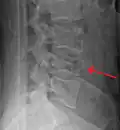

A burst fracture of L4 as seen on plane X ray -

A burst fracture of L4 as seen one plane X ray -